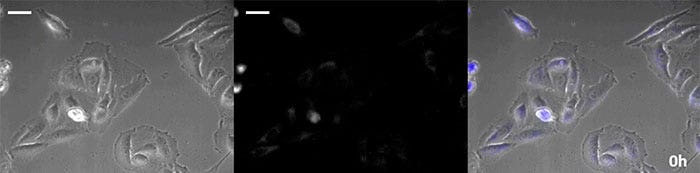

La luciférine de type coelenterazine a une luminosité particulièrement élevée, mais, comme elle s’oxyde assez rapidement dans la cellule, il est nécessaire d’en ajouter régulièrement lors des observations de longue durée. Pour résoudre ce problème, nous avons perfusé des cellules exprimant une protéine luminescente de haute intensité avec du milieu de culture tandis qu’un dispositif d’ajout de substrat automatisé ajoutait automatiquement de la coelentérazine afin que la luminescence puisse être suivie en continu. Nous avons ainsi réussi à suivre les effets d’un médicament en prenant des images de la luminescence en combinaison avec des images en contraste de phase pendant plus de 24 heures (figure 4).

0 heure

Figure 4-1 0 heure

6 heures

Figure 4-2 6 heures